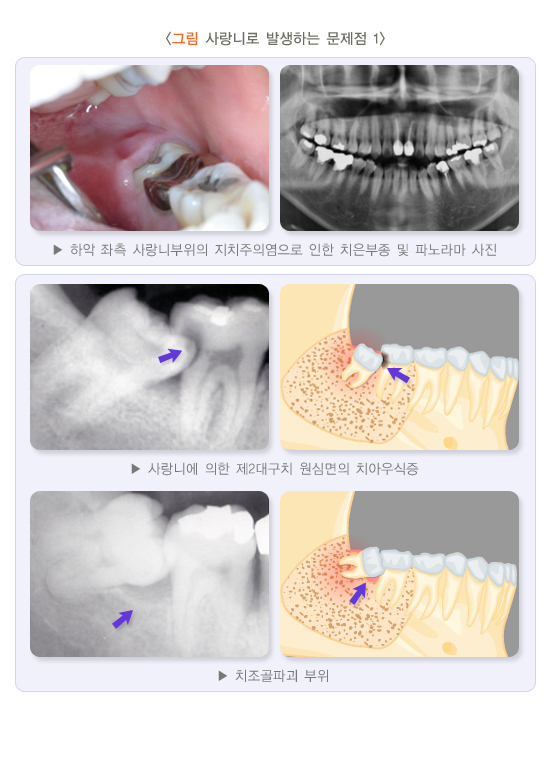

사랑니 주변의 염증이 반복되면 얼굴과 목이 부을 정도로 심해질 수 있으므로 사랑니 주변의 통증이 있다면 염증 치료와 더불어 발치하는 것이 좋습니다. 매복된 사랑니로 인해 흔히 물주머니 또는 물혹이라고 하는 함치성 낭종이 생겨 주변 턱뼈가 파괴되고, 더욱 진행되면 주변 어금니로 확산되어 치아의 생존력이 없어질 수 있습니다.

(5) 제2대 구치(두 번째 큰 어금니) 원심면(뒷부분) 치아 병변

사랑니가 앞쪽 방향으로 기울어 매복되면 앞 어금니 뒤쪽 면에 음식물이 쉽게 끼어 치아우식증이 생기기 쉽고, 진행되면 통증이 생길 수 있습니다. 어금니 치아우식증이 진행되면 사랑니 발치 시 약해진 치아가 부서지기도 합니다. 통증 감소와 치아 손상 방지를 위해 발치 전 또는 발치 후 어금니의 치료가 필요할 수 있습니다. 대개 근관(신경) 치료를 포함하여 보존 및 보철치료를 하게 됩니다. 사랑니가 옆으로 누워있으면 앞 어금니의 뿌리가 흡수되는 경우가 있습니다. 사랑니에 의해 이미 손상된 치아는 사랑니의 발치 전후로 정밀한 검사가 필요합니다. 손상이 매우 심하면 앞의 어금니를 뽑기도 합니다. 치아가 시리거나 아프거나 다른 증상이 있다면 이미 앞의 어금니가 손상되었을 가능성이 높습니다.